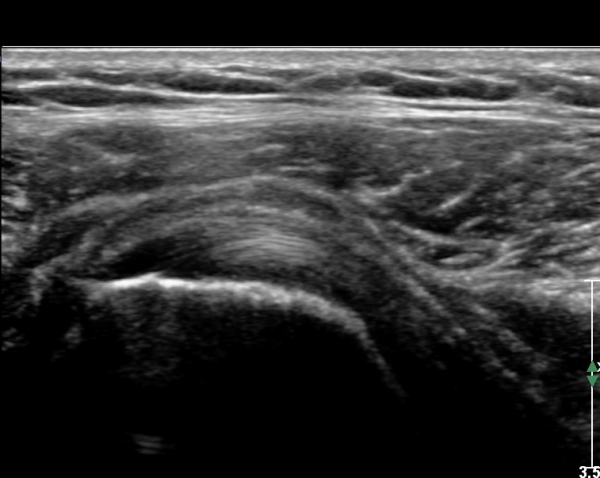

Å½ÃËÀÚ¸¦ Á»´õ ¸»´ÜÀ¸·Î À̵¿ ÈÄ(¶Ç´Â ¾Æ·¡·Î ±â¿ïÀÎ ÈÄ) ³»ÃøºÎ¸¦ Á¶ÀýÇÏ´Ï °ß°©ÇϱٰÇ

Ç¥ÃþÀ¸·Î Á¡¾×³¶³» ¼ö¾×Àú·ù°¡ °üÂûµÈ´Ù(»çÁö 3, 4). ŽÃËÀÚ¸¦ Á¶Á¤ÇÏ´Ï ÀÌµÎ¹Ú°Ç ÁÖÀ§ ¼ö¾× Àú·ù¿Í

Á¡¾×³¶³» ¼ö¾×Àú·ù°¡ °üÂûµÇ¾î Á¡¾×³¶¿°°ú Ȱ¾×¸·¿°ÀÌ ÀÖÀ½À» ¾Ë ¼ö ÀÖ´Ù(»çÁø 5).